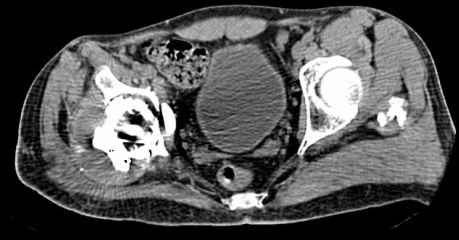

Мужчина, 45 лет. 6 мес. назад перенес тотальное эндопротезирование правого тазобедренного сустава по поводу ложного сустава шейки бедра.

Характер реконструкции вертлужной впадины не известен. Через 3 мес. после операции отметил щелчки и хруст при движениях в области эндопротеза. В анамнезе туберкулез легких. Сейчас, по заключению фтизиатра, в легких активного процесса нет. Местного воспаления нет.Предполагается нестабильность чашки в связи с бактериальным воспалением. Планируется удаление чашки и цемента, пластика дна измельченными аутотрансплантами и гидроксилапатитной керамикой, затем кольцо Мюллер, цементная чашка.

Смущает и ножка - зона просветления вокруг мантии. Предложения по тактике?

Мне кажется, что необходимо сначала выполнить пункцию, и принимать решение о тактике - исходя из результатов посева полученного пунктата.

И еще, в случае одномоментного реэндопротезирования здесь показана имплантация кольца Бур-Шнайдера (ИМХО)

прямо скажем, очень загадочная конструкция с проволокой и винтами. :) На основании чего Вы подозреваете септическую нестабильность? Каковы результаты анализов? Согласен с доктором - нужно сделать пункцию. Есть ли снимки до и сразу после операции? Знаете ли Вы диаметр головки,какой будет внутренний диаметр Вашей чашки? Известно ли, чей протез? Может есть смысл найти автора работы и узнать о подробностях установки протеза?